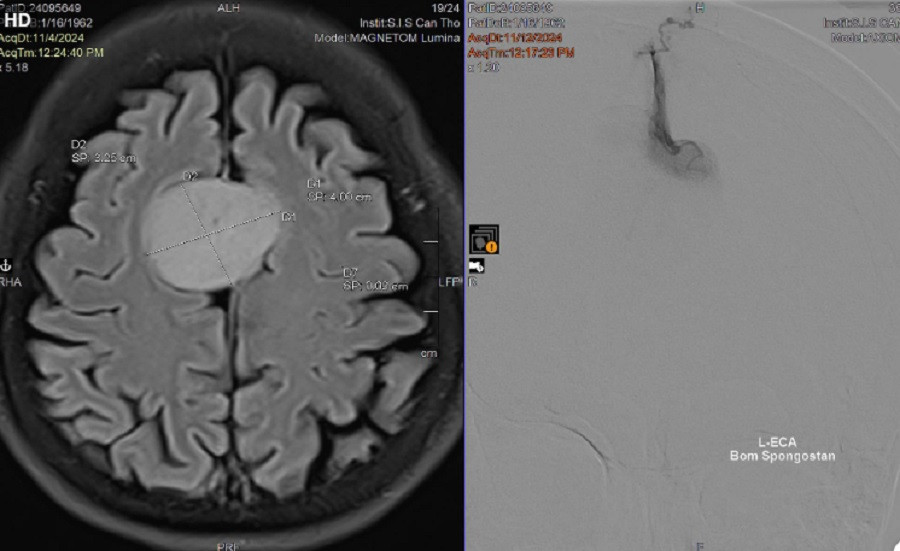

| Khối u não có kích thước lớn nằm giữa đỉnh đầu của người bệnh |

Tuy nhiên, trên hình ảnh kiểm tra ghi nhận, bệnh nhân có khối u não kích thước lớn (35 x 40mm) nằm giữa đỉnh đầu, chấn thương do tai nạn không liên quan đến khối u này. Tai nạn giao thông trở thành tình huống may mắn giúp bệnh nhân được chẩn đoán, điều trị khối u não. Để tránh biến chứng nguy hiểm đến tính mạng của người bệnh, các bác sĩ đã thực hiện tắc mạch, phẫu thuật loại bỏ khối u.